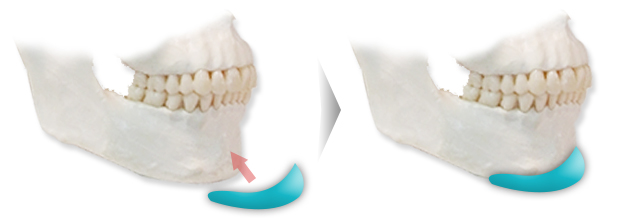

| 주걱턱 수술 |

턱끝 뼈가 과성장한 턱끝 비대증의 경우, 턱 끝을 수평 절골술을 통해 길이를 줄이고 턱끝을 후방으로 이동시켜주는 수술로 주걱턱 교정이 가능합니다. 위, 아래의 치아를 맞물리게 입을 다물었을 때 치열상태는 정상인 경우에 주걱턱 교정이 가능한 수술방법입니다. |